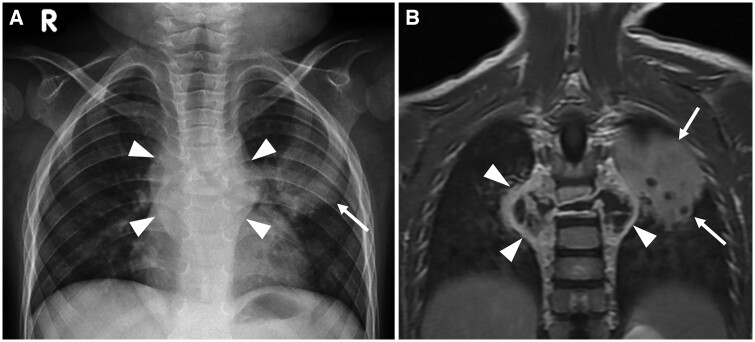

Tuberculosis (TB) remains the leading cause of death from a single infectious agent globally, despite being a potentially curable disease. This disease typically affects the lungs but may involve many extrapulmonary sites, especially in patients with risk factors such as HIV infection. The clinical features of extrapulmonary TB may mimic many different disease entities, particularly at less common thoracic sites such as the heart, chest wall, and breast. Imaging has an important role in the early diagnosis of TB, helping to detect disease, guide appropriate laboratory investigation, demonstrate complications, and monitor disease progress and response to treatment. Imaging supports the clinical objective of achieving effective treatment outcome and complication prevention. This review aims to highlight the imaging spectrum of TB affecting both pulmonary and extrapulmonary sites in the thorax. We also briefly provide key background information about TB, such as epidemiology, pathogenesis, and diagnosis.